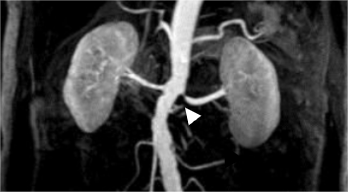

▲左肾动脉近段狭窄

“这是正常的肾动脉,这是患者徐阿姨的肾动脉。左肾动脉开口处有狭窄。”影像中心袁晨主任表示,非增强型肾动脉磁共振血管显像技术(NE-MRA)是一种安全、无创、准确的检查方式。对高血压、肾动脉狭窄等患者的明确诊断有着重要临床意义。

为了明确病因,精准治疗。结合徐阿姨的临床表现和病史,专科医生给出肾动脉血管成像检查的建议。得知徐阿姨不能使用碘造影剂又不想进行肾血管介入的有创检查,广济医院影像中心为其安排了“非增强型肾动脉磁共振血管显像技术(NE-MRA)”,仅仅花了10来分钟,就获得了患者双侧肾功能清晰的MR图像,快速了解其双肾及肾上腺情况,为临床诊疗提供了重要的影像信息。